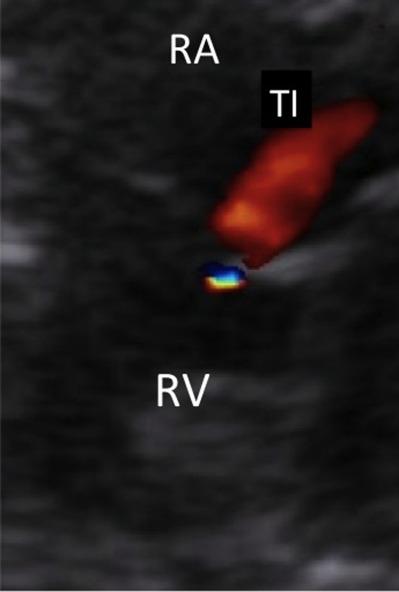

Fetal circulation has characteristic features, being morphologically and functionally different from extrauterine circulation. The ductus arteriosus plays a fundamental role in directing the blood flow to fetal inferior body parts. Basically, the ductus arteriosus directs 80-85% of the right ventricular output arising from the superior vena cava, coronary sinus, and a small part from the inferior vena cava to descending aorta. Its histological structure is made up predominantly by a thick muscular layer, differently from the aorta and the pulmonary artery, which increases with gestational age. The fibers have a circumferential orientation, especially at the external layers, facilitating and making effective ductal constriction. These factors may generate lumen alterations which may cause fetal and neonatal complications, such as heart failure, hydrops, neonatal pulmonary hypertension, and even death. Classically, maternal administration of indomethacin and/or other antiinflammatory drugs interfere in prostaglandins metabolism, causing ductal constriction. However, many cases of fetal ductal constriction, as well as of persistent neonatal pulmonary artery hypertension, remain without an established etiology, being referred as "idiopathic." In recent years, a growing body of evidence has shown that herbs, fruits, nuts, and a wide diversity of substances commonly used in daily diets have definitive effects upon the metabolic pathway of inflammation, with consequent inhibition of prostaglandins synthesis. This antiinflammatory action, especially of polyphenols, when ingested during the third trimester of pregnancy, may influence the dynamics of fetal ductus arteriosus flow. The goal of this review is to present these new observations and findings, which may influence dietary orientation during pregnancy.

胎儿循环具有独特的特征,在形态和功能上与宫外循环不同。动脉导管在引导血液流向胎儿身体下部起着重要作用。基本上,动脉导管将来自上腔静脉、冠状窦以及一小部分下腔静脉的右心室输出量的80%-85%导向降主动脉。其组织结构主要由一层厚厚的肌肉层组成,这与主动脉和肺动脉不同,且会随着孕周增加。纤维呈圆周方向排列,尤其是在外层,有助于并使导管有效收缩。这些因素可能导致管腔改变,进而引起胎儿和新生儿并发症,如心力衰竭、水肿、新生儿肺动脉高压,甚至死亡。传统上,孕妇使用吲哚美辛和/或其他抗炎药物会干扰前列腺素代谢,导致导管收缩。然而,许多胎儿导管收缩以及持续性新生儿肺动脉高压的病例仍病因不明,被称为“特发性”。近年来,越来越多的证据表明,草药、水果、坚果以及日常饮食中常用的多种物质对炎症代谢途径有确切影响,从而抑制前列腺素合成。这种抗炎作用,尤其是多酚类的抗炎作用,在妊娠晚期摄入时,可能会影响胎儿动脉导管的血流动力学。本综述的目的是介绍这些新的观察结果和发现,它们可能会影响孕期的饮食指导。